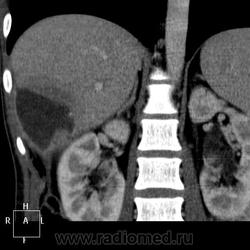

КТ (часть кадров выложу позже ). Цель направления на КТ - образование правой доли печени, исключить образование тела п.ж.

). Цель направления на КТ - образование правой доли печени, исключить образование тела п.ж.

Жаль, что я в этом ничего не понимаю!Вижу образование в печени, похожее не гемангиому;желчные протоки расширены ( холангио-целюлярный?).Почки не первой " свежести".Картинки непривычные для глаза-только к МРТ-сканам начала привыкать.

Гемангиома, являясь сосудистой опухолью, будет такого же цвета, как и сосуды, во все фазы. Это - кистовидное образование, стенки относительно равномерной толщины, копящие контраст тонкой полоской. Содержимое образования жидкостной плотности и контраст не копит.

Гепатоспленогмегалия. Начальная портальная гипертензия, холедох не расширен. В воротах печени бугристая масса.... чего? Кальцинаты поджелудочной железы, мелкий камушек в желчном. Вопрос в том, что за кистовидное образование, что за полоса-серп вокруг желчного пузыря, что в воротах печени. Опухоли п.ж. я не нашла.

Данному пациенту в заключении я выставила подпеченочный абсцесс, гепатоспленомегалию, портальную гипертензию, конгломерат лимфоузлов ворот печени, лимфаденопатию желудочной группы л/у, хр.калькулезный панкреатит, ЖКБ с перихолециститом.

В воротах, похоже л/у, а жидкостное абсцесс печени.

Абсцесс печени.